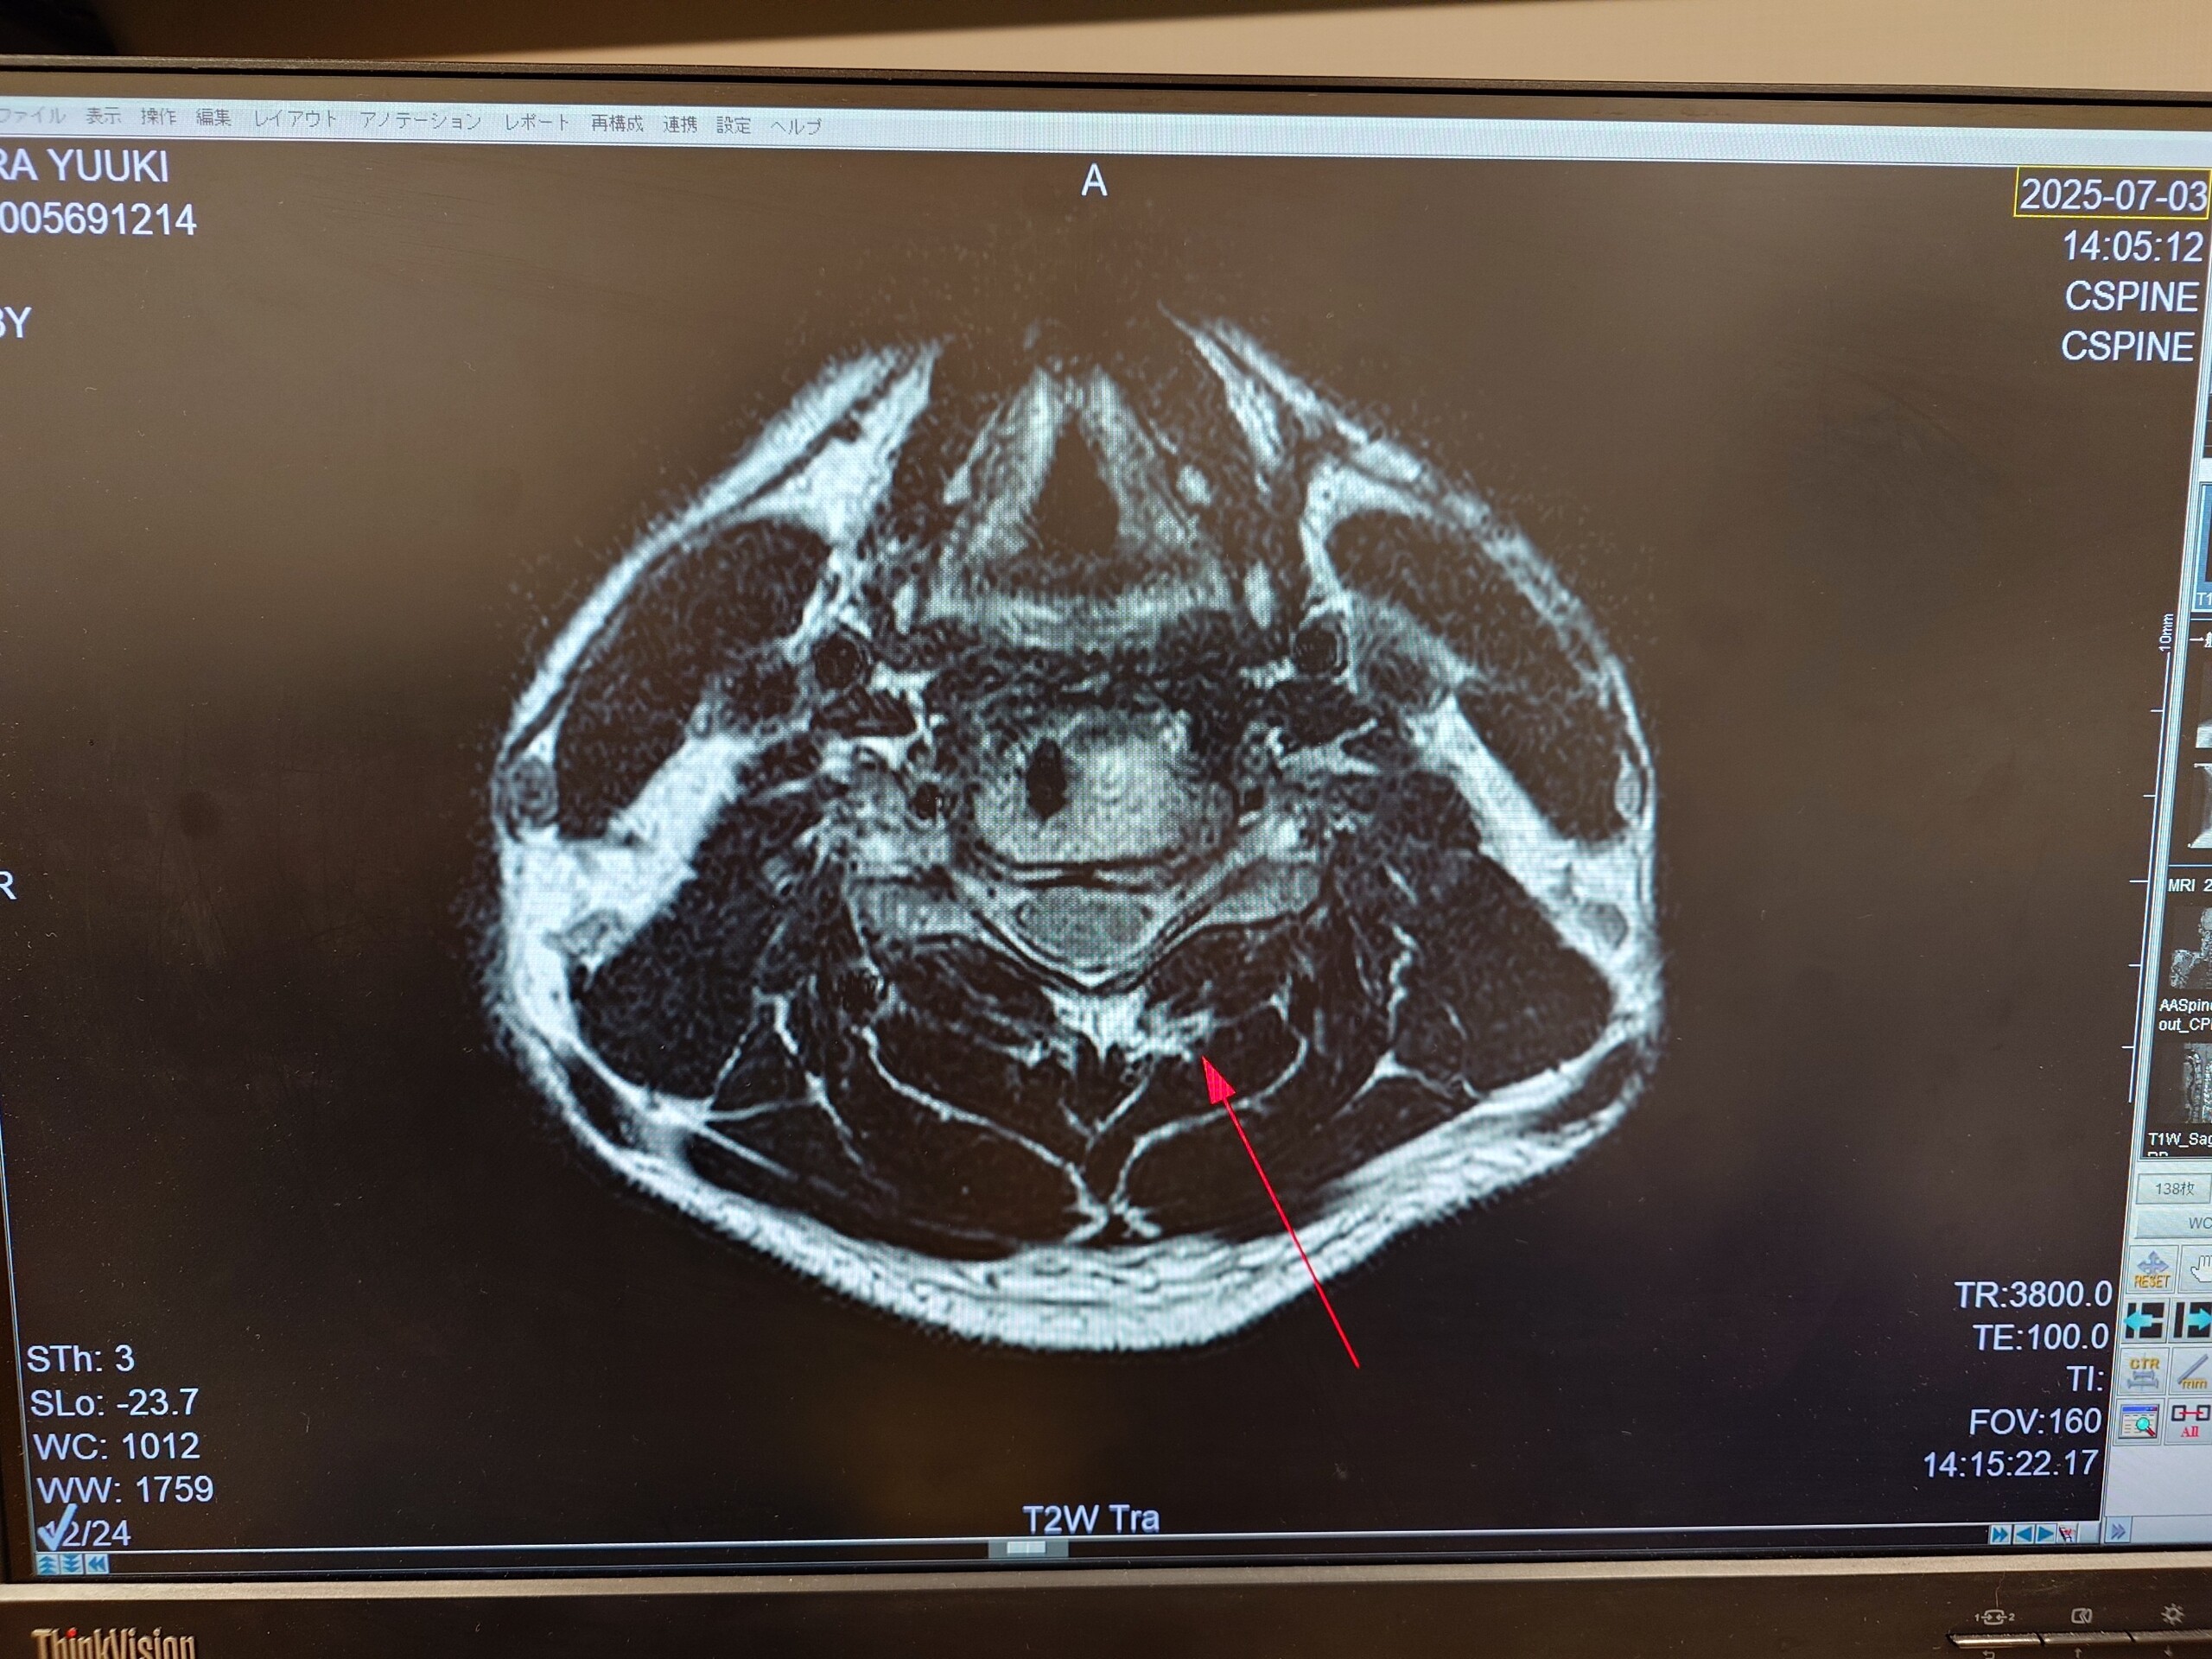

病院🏥に行き少し休んでおりました🙇

首の炎症にブロック打って貰い回復!!